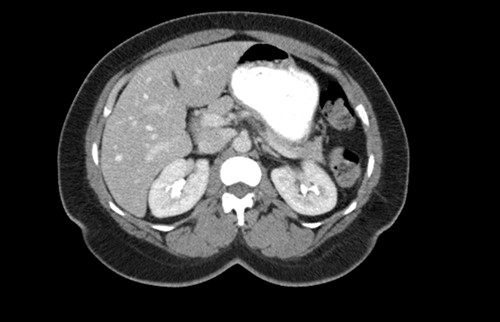

CT scan of the abdomen showing the absence of the gallbladder within the gallbladder fossa. This image also depicts the absence of malrotation of the gut or horseshoe kidney.

agenesis as seen in Fig. 1. The port sites were sutured closed, and no post-operative complications were noted. It was concluded that the adhesions were causing the patient’s chronic abdominal pain which resolved. A computed tomography (CT) scan of the abdomen seen in Figs 2 and 3 confirmed the absence of a gallbladder with no associated pathology depicted.